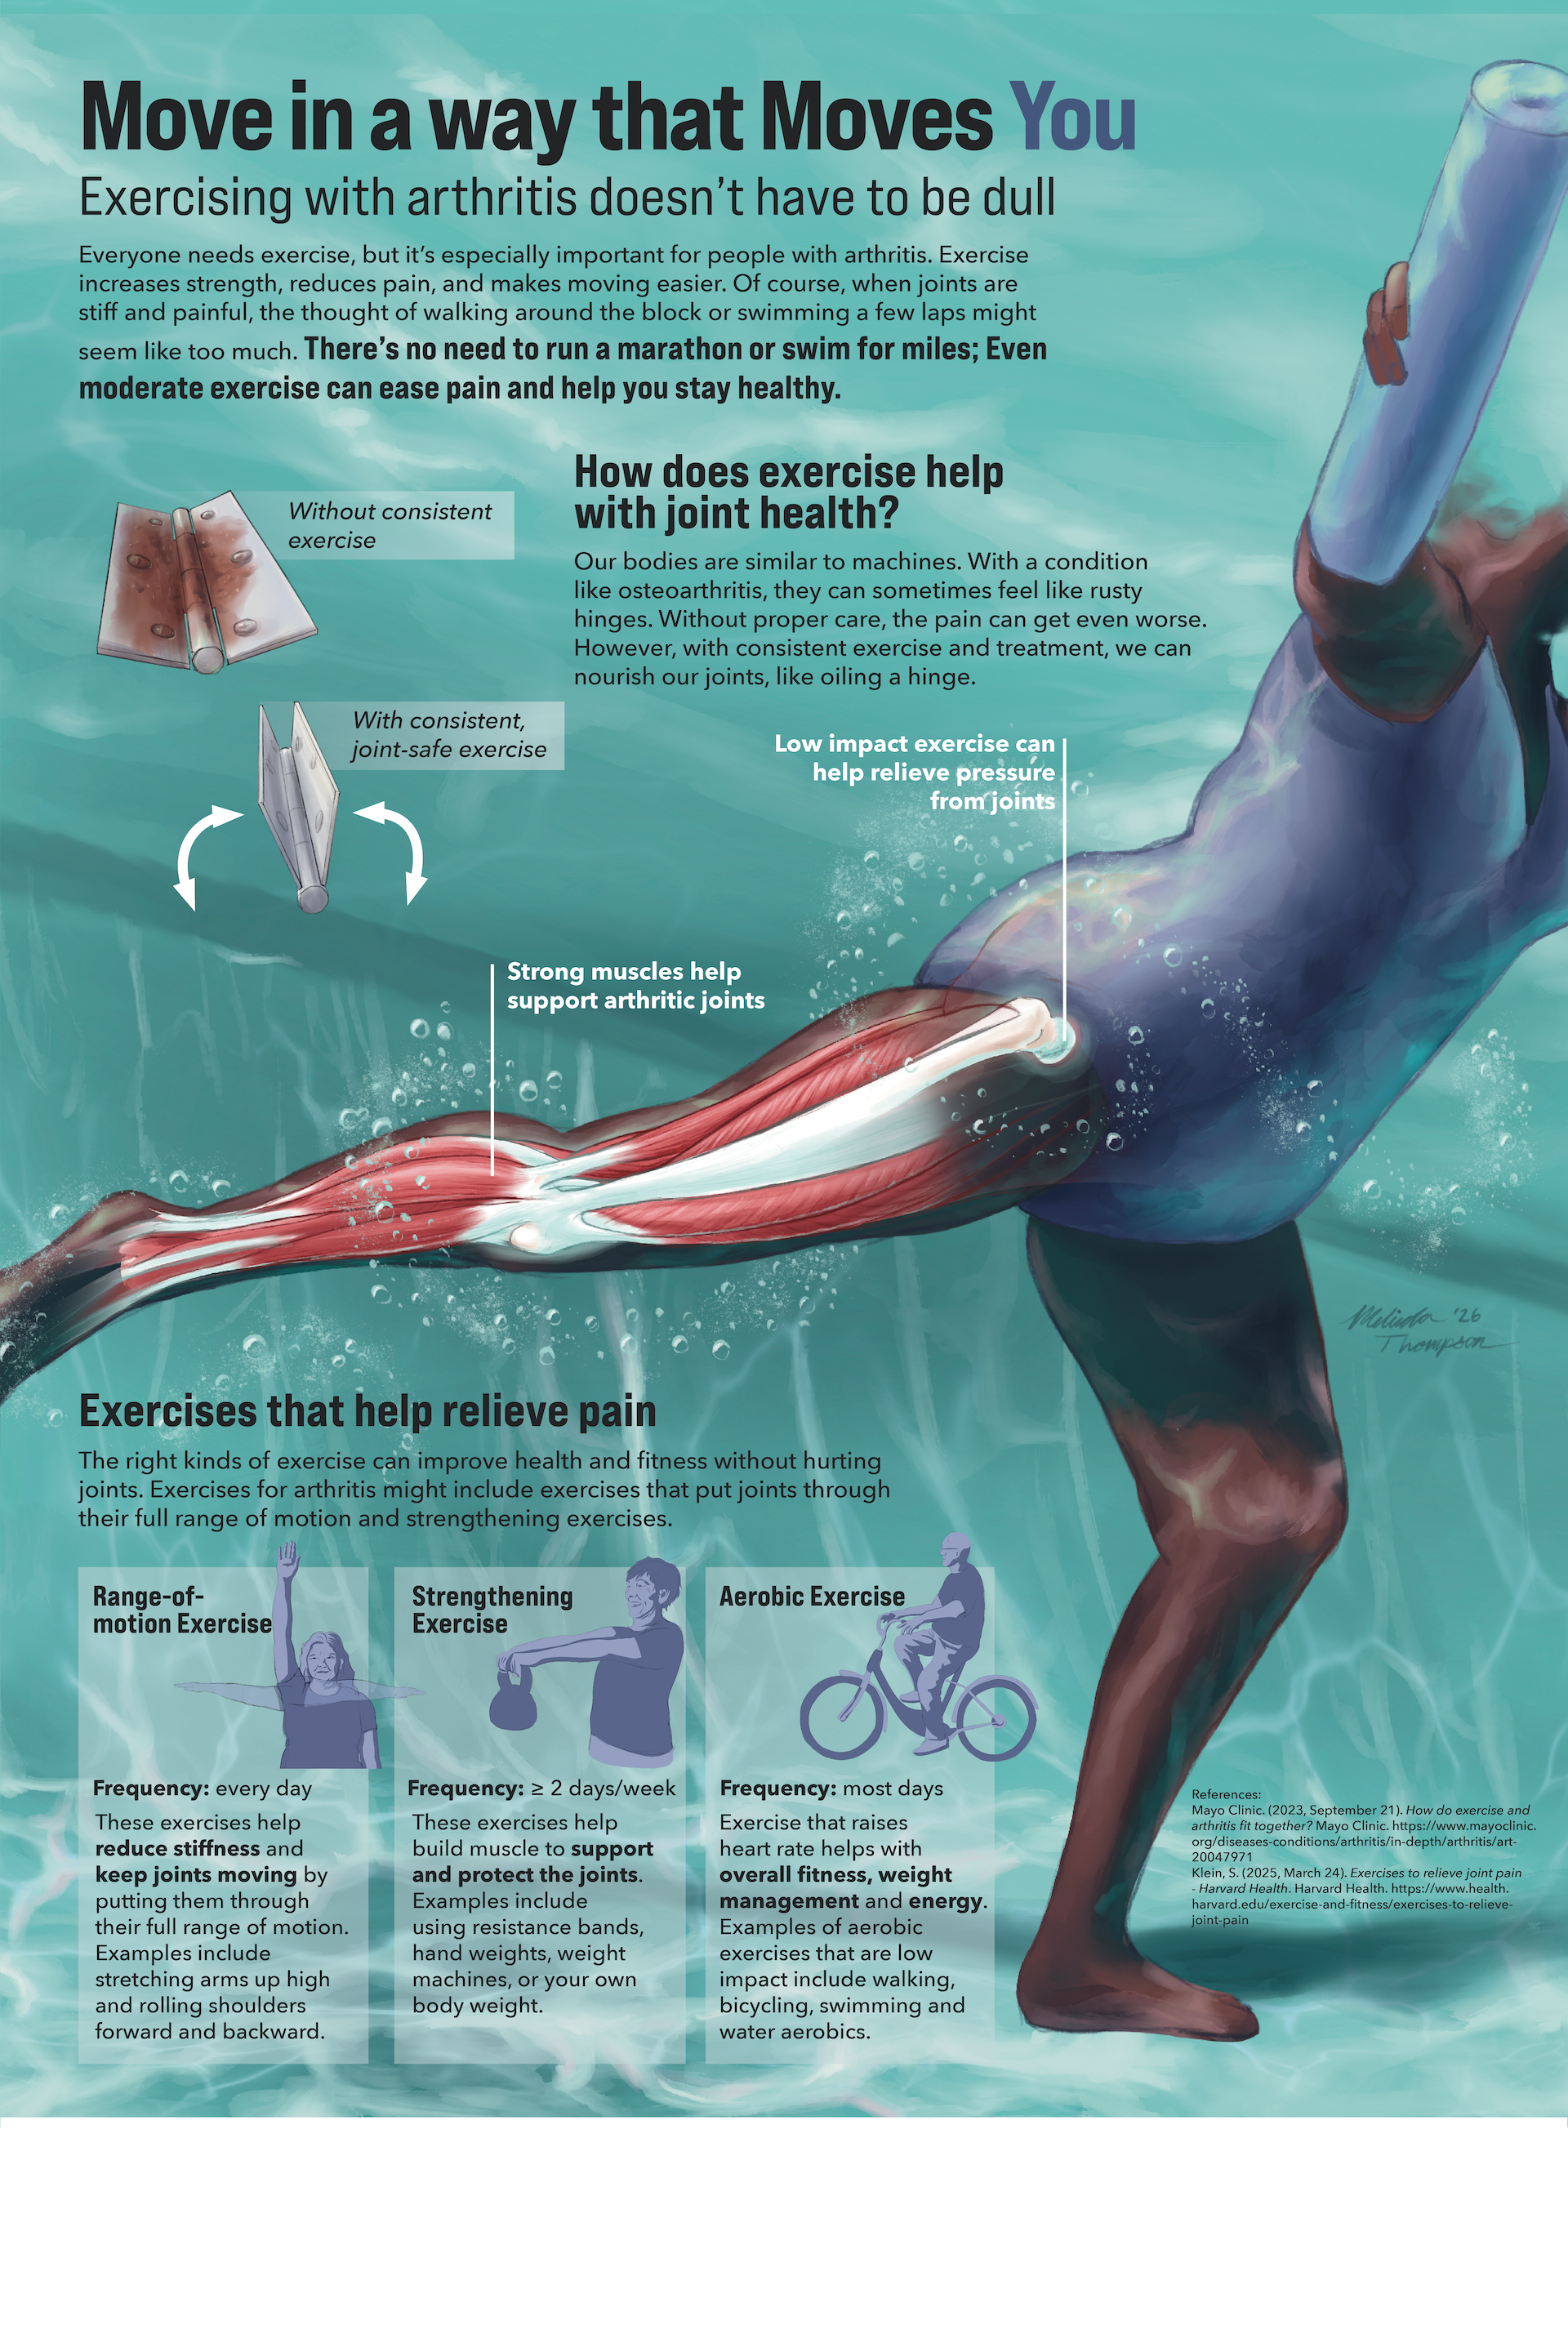

Cardiac Rehab Clinical Poster: Move in a way that Moves You